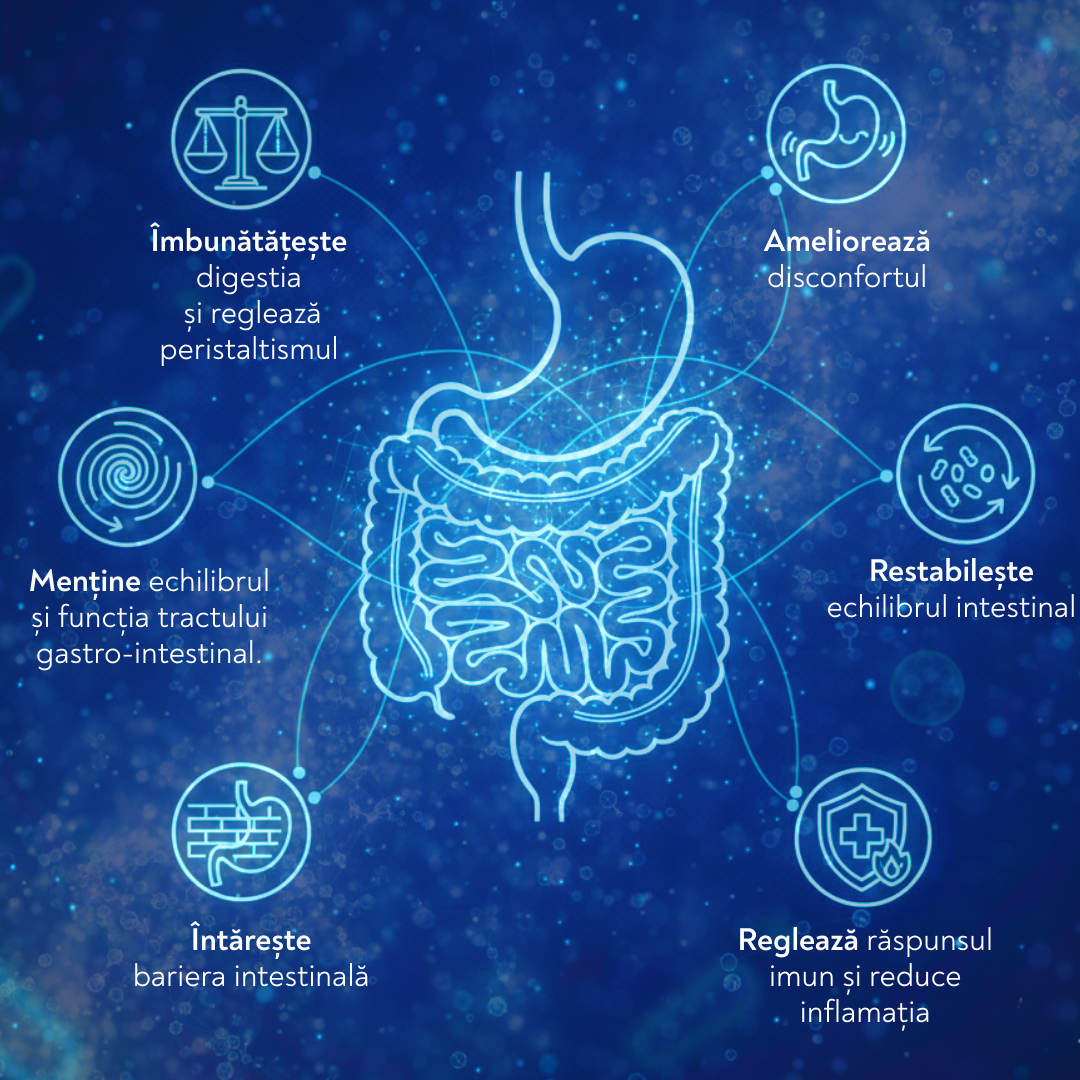

Acest postbiotic Bibiotic® Gastro, ca un puternic regulator al microbiotei, este un remediu eficient împotriva disbiozei. Una dintre principalele probleme ale epocii noastre este disbioza intestinală. Tractul nostru intestinal este populat de trilioane de microorganisme de diferite tipuri. Iar fiecare specie îndeplinește funcții strict definite, reprezentând o verigă dintr-un lanț metabolic foarte complex. Chiar și microorganismele dăunătoare îndeplinesc roluri utile. De exemplu, acestea antrenează sistemul imunitar și îl mențin activ. De aceea nu există bacterii bune și rele. Iar echilibrul dintre ele este important. Starea normală și echilibrată a microbiotei se numește normobioză sau eubioză. Perturbarea echilibrului florei intestinale, în care unele microorganisme își măresc populația în detrimentul altora, se numește dezechilibru microbian sau disbioză. Prin urmare, se perturbă conținutul cantitativ și calitativ al metaboliților produși de bacterii. Acest lucru duce la apariția diferitelor afecțiuni de sănătate, cum ar fi balonare, gaze, spasme, diaree, constipație, dureri abdominale, oboseală, reacții alergice, flatulență, funcție imunitară afectată etc. Cauzele dezvoltării disbiozei pot fi de diferite naturi – absorbția de toxine din mediul înconjurător poluat, situații de stres, malnutriție, utilizarea de antibiotice și alte medicamente, insuficiență imunitară, parazitoză, consumul de alimente care conțin pesticide, conservanți și alte substanțe antibacteriene și multe altele. Pentru a combate disbioza și a restabili echilibrul florei intestinale, trebuie pur și simplu să restabilim echilibrul metaboliților bacterieni. La rândul lor, acestea inhibă rapid și eficient dezvoltarea speciilor bacteriene în creștere și favorizează dezvoltarea celor în scădere.

Prin administrarea postbioticului Bibiotic® Gastro, organismul primește toți metaboliții bacterieni necesari pentru a depăși afecțiunea de disbioză.

Prin administrarea postbioticului Bibiotic® Gastro, organismul primește toți metaboliții bacterieni necesari pentru a depăși afecțiunea de disbioză.